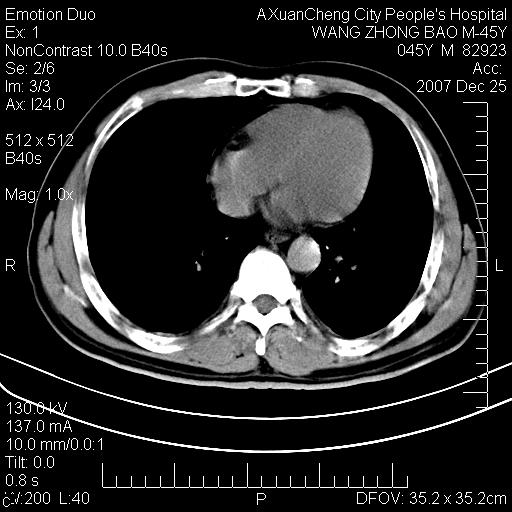

以下是引用卜一在2007-12-25 14:07:00的发言:[br]胰头钩部略增大,与十二指肠壶腹部关系密切,其内明显见软组织密度肿块,明显强化,但肠壁较光滑 柔软。考虑:炎性增生!建议消炎后复查!待除外壶腹部腺癌!

以下是引用qiuleiyu在2007-12-25 18:14:00的发言:[br]胰腺增大,周边渗出改变,肾前筋膜明显增厚,示少量积液.胆囊壁毛糙,周边少许渗出,胆总管壁厚,异常强化,然扩张不明显.结合病程急短;考虑;胆管炎,胆囊炎,胆源性胰腺炎可能大,请结合实验室检查及随访.

以下是引用lisihao在2007-12-25 14:23:00的发言:[br]急性水肿型胰腺炎[br]依据:1、胰腺弥漫性肿大,边缘稍毛糙;[br] 2、双侧肾周筋膜增厚,尤以左侧为甚(重要征象)[br] 3、双侧后胸膜增厚(刺激性炎症);[br] 4、结合病史,查血尿淀粉酶应该可以确诊。